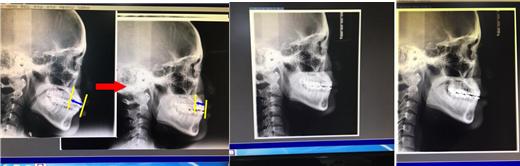

예전이랑 한번 비교해보면,

왼쪽부터 과거->현재 순서의 엑스레이입니다 ㅋㅋ

처음엔 입 진짜 많이 나와있었죠 ㅋㅋㅋ

처음이 교정 전이구요, 두 번째 사진이 1년 됐을 때! 이때까지 정말 드라마틱한 변화가 있었음 ㅋㅋ

그 다음이 1년 반쯤된 시점이구, 맨 오른쪽 사진이 2년쯤 된 현재의 모습!

1년이 지난 뒤부터는 앞니를 자연스럽게 빼주신 것 같기도 하구요...!!!!